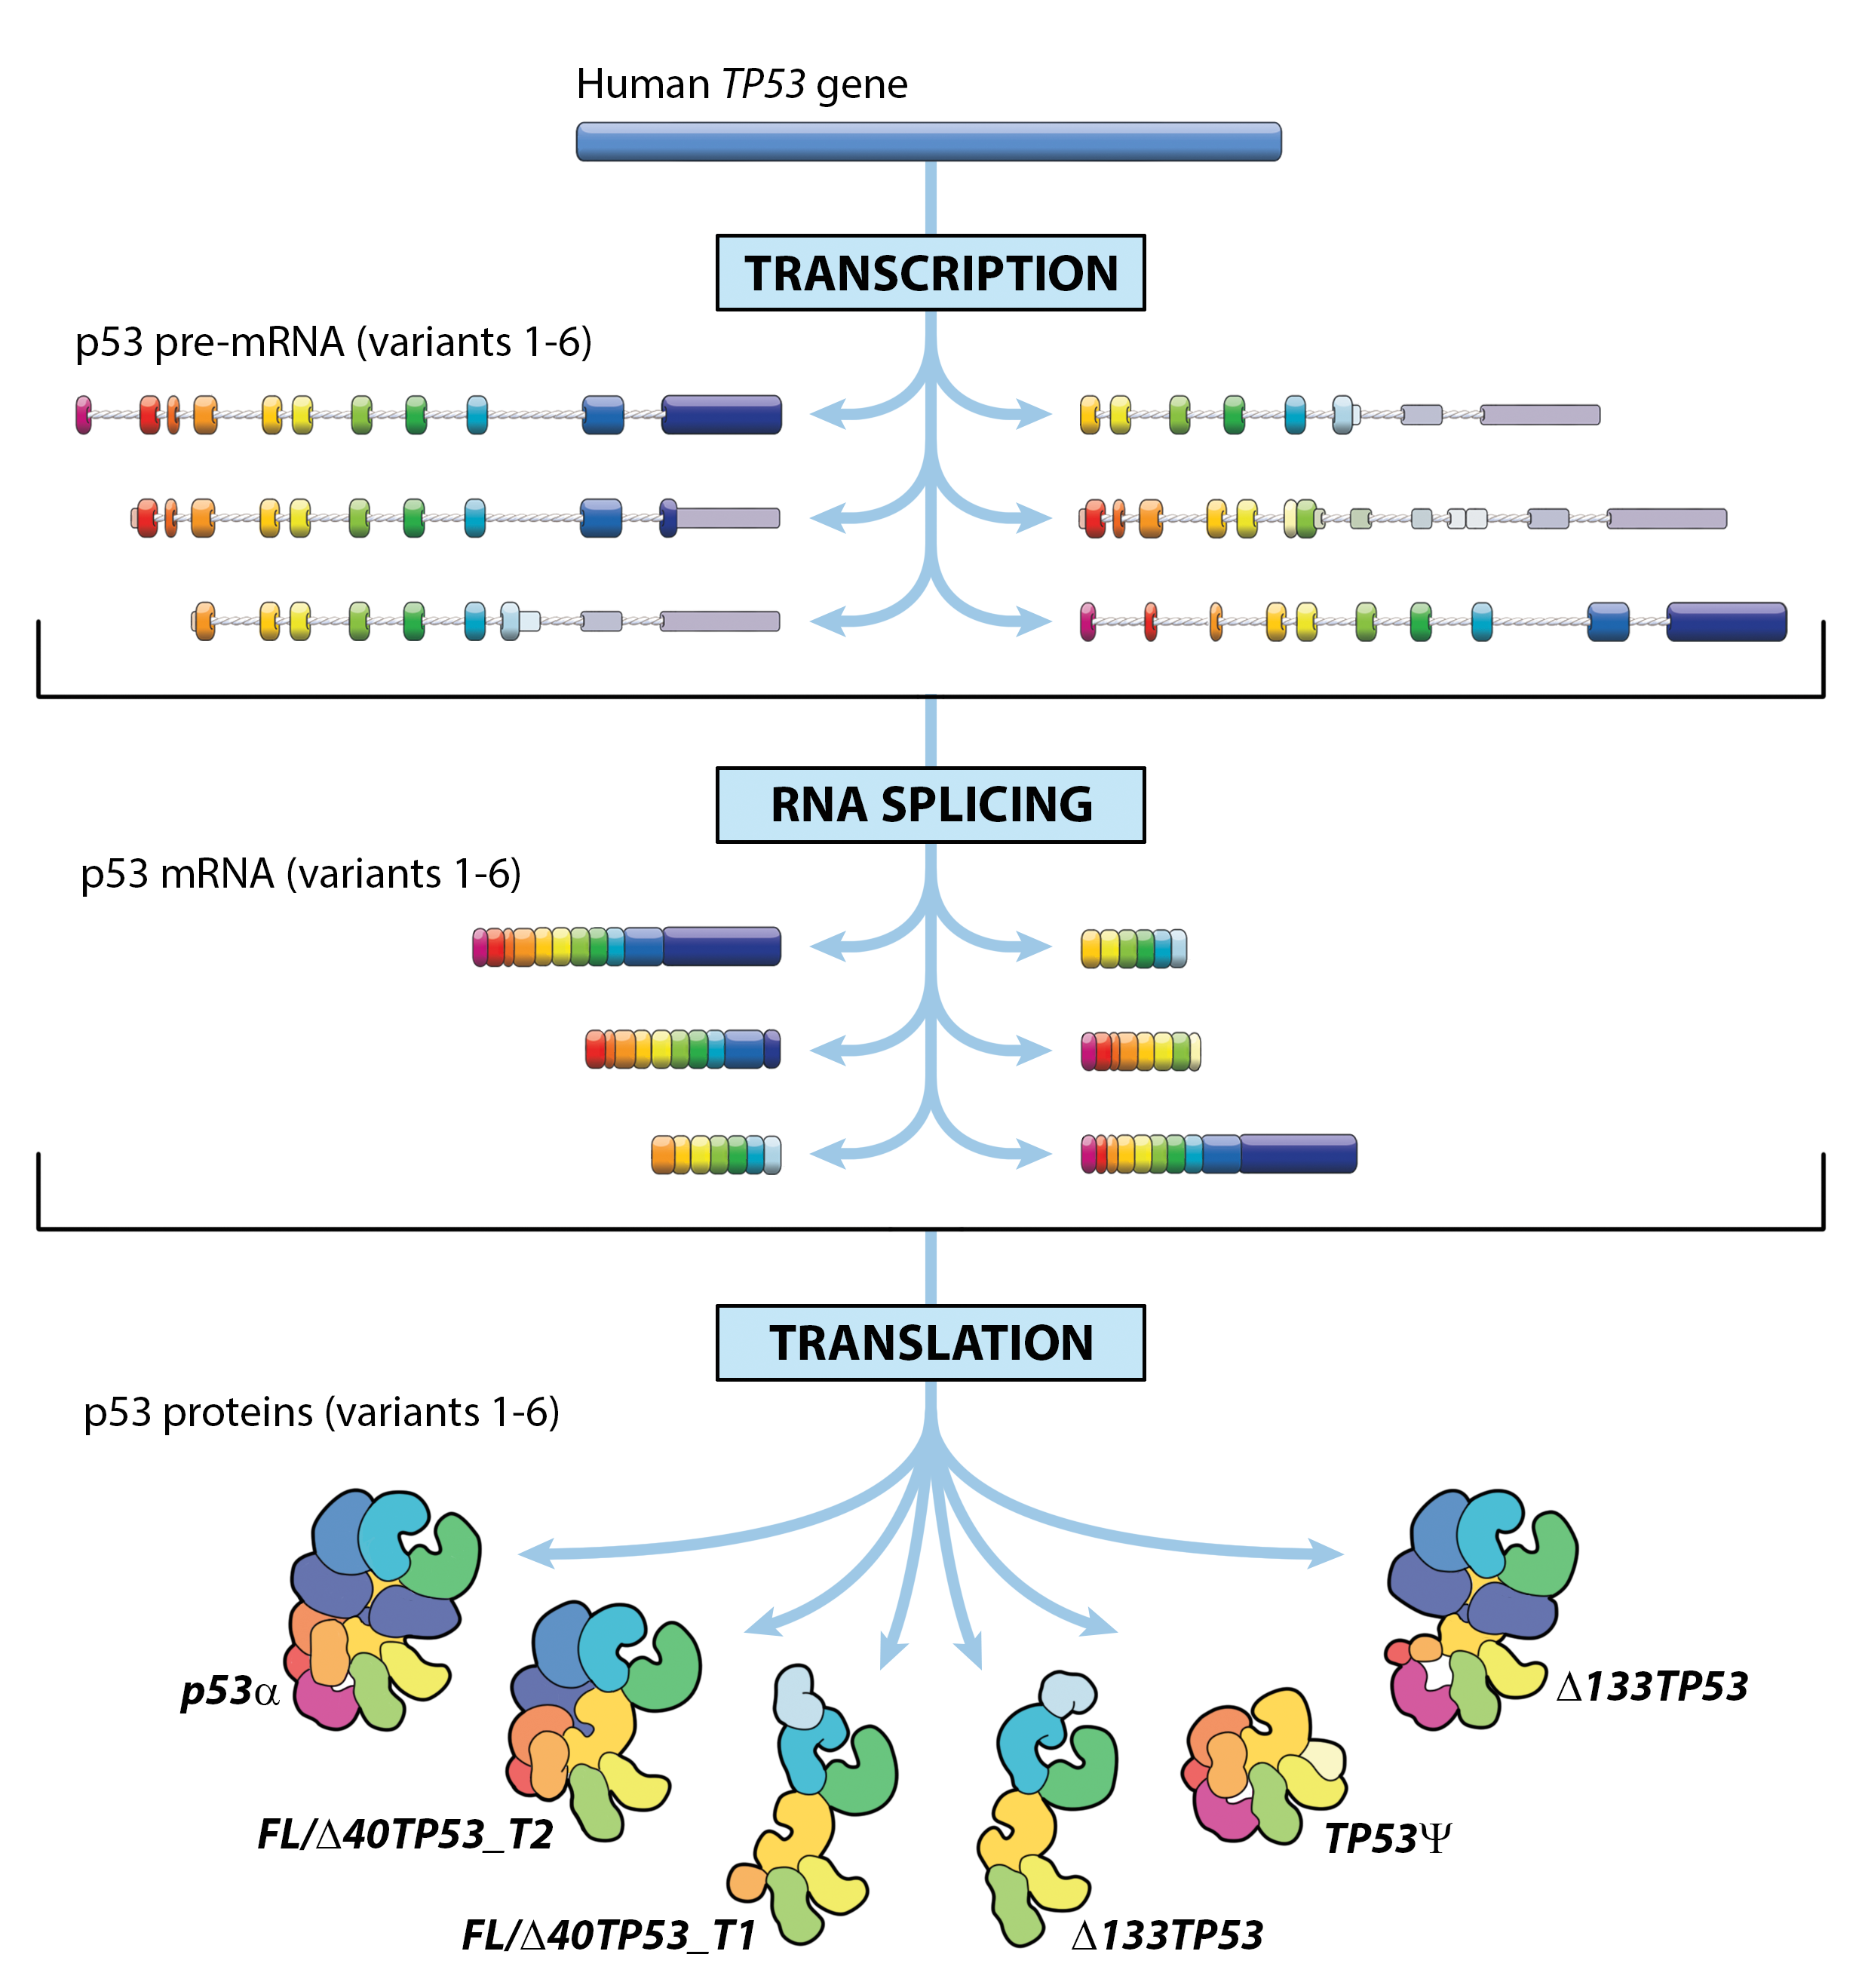

One cancer gene – but several different proteins

Cancer arises due to changes in DNA in a single cell. Many changes are needed over time to a cell’s DNA to make it cancerous – which is why cancer is usually a disease of later li

The tumour-promoting activities of a famous protein

Developing new cancer therapies and a more reliable test for prostate cancer are just some of the potential outcomes of Maurice Wilkins Centre research into the cellular mechanisms